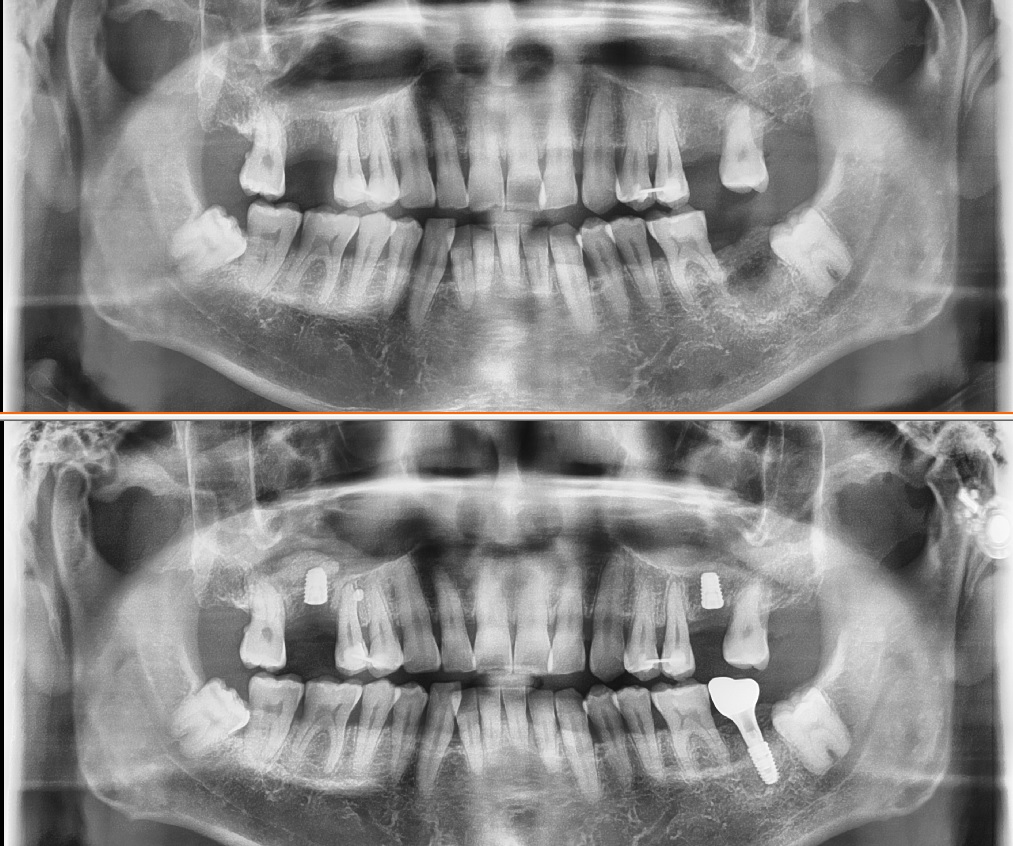

아래 사진은 수면임플란트 시술을 받으신 사진인데요

위 환자분은 세군대의 임플란트를 모두 세번의 수면으로 시술 받은 케이스 입니다

한번에 다 시술을 받는다는건 불가능합니다

위 사진은 다수의 임플란트를 레미마졸람으로 마취후

1시간 내외의 시술시간으로

디지털 가이드 임플란트를 시술한 사진입니다

이 환자를 수면마취를 하고 저렇게 다수의 임플란트를

비절개 수술이 아닌 절개의 수술로 했다면 엄청난 양의 출혈이 환자의 기도에 지속적으로 자극을 줄 것입니다

확실히 출혈이 적기때문에

환자의 호흡이 원활하고

그리고 시술시간이 굉장히 줄어드는 장점도 있습니다

물론 1시간 30분의 시간중에 수면시간은 1시간 정도

그리고 나머지 20분정도는 마취를 깨우면서 시술을 하였습니다 .